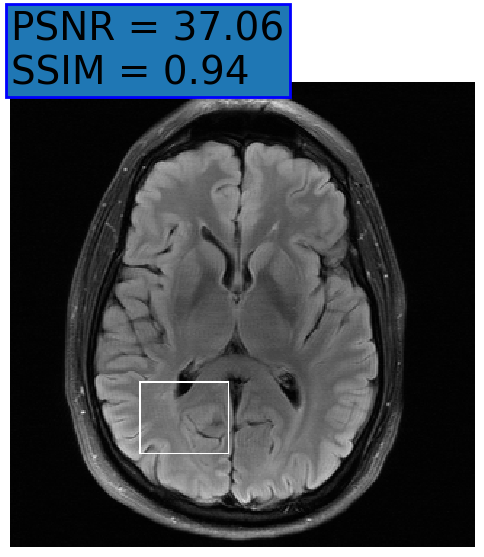

Figure 3: Reconstructions results. Rows 1 and 3: Examples of comparing the ground truth (GT) fully sampled image to the reconstructed images obtained by the three models (1-3), NPB-REC, baseline, E2E-VarNet trained with Dropout, and the NPB-REC std. map at accelerations R=4𝑅4R=4, R=8𝑅8R=8, respectively. Rows 2 and 4: The corresponding annotated ROIS of Nonspecific white matter lesions.

Fig. 3 presents examples of reconstruction results obtained by (1) our NPB-REC approach, (2) the baseline, and (3) Monte Carlo Dropout, for equispaced masks with two different acceleration rates R=4𝑅4R=4 and R=8𝑅8R=8. The reconstructed images predicted by the three models are smoother than the reference image. This is due to the fact that all the models were trained with SSIM loss, which tends to produce overly smooth reconstructions while preserving the diagnostic content and the anatomical features Sriram et al. (2020a). These images can be enhanced by dithering the image by adding a small amount of random Gaussian noise to produce a more textured reconstruction, as proposed in Sriram et al. (2020b).

Table 1 presents the mean PSNR and SSIM metrics, calculated over the whole inference set, for the three models. Our NPB-REC approach achieved significant improvements over the other methods in terms of PSNR and SSIM (Wilcoxon signed-rank test, pmuch-less-than\ll1e-4, except for SSIM values in line W, R=4𝑅4R=4 where they are roughly the same for NPB-REC and Baseline). The improvement in the reconstruction performance can be noted both quantitatively from the metrics, especially for masks with acceleration rate R=8𝑅8R=8, and qualitatively via the images of annotations, where our results show less smoothness than those obtained by Dropout.